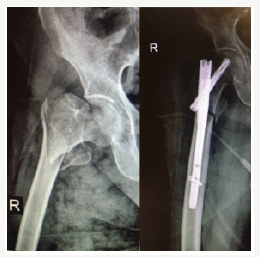

Total number of patients were 83. about 49 women and 34 man. After one year we assessed mortality rate As we got, 24% (20 patients) mortality rate after one year and 6% (3 man and 2 women) death in first month. Of this number (20 patients) 12 were women (14.4%) and 8 were man (9.6%) (Figure 1-4).

Figure 2:OTA/31A2.

Figure 3:OTA/31A2.